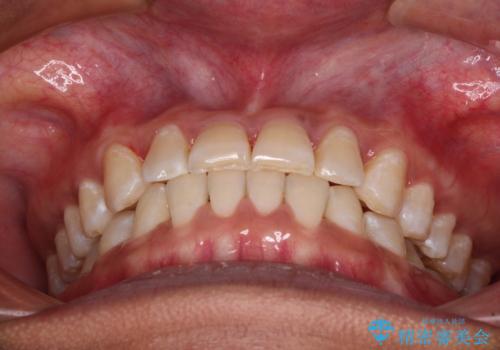

反対咬合の改善 途中で出産をしながらワイヤー矯正

- 前歯の隙間と反対咬合を気にして来院された患者様です。

マウスピース矯正も提案しましたが、しっかりと使用する自信がないとのことで、ワイヤー装置により矯正治療を行うこととしました。

咬合力が強く、反対咬合の改善に時間がかかりましたが、その後はスムーズに進めることができました。

途中、妊娠と出産があり、治療が中断したため、治療期間は延びましたが、出産も矯正治療も無事に終えることができました。